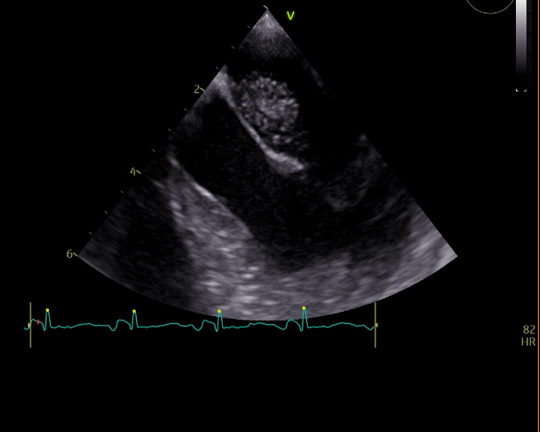

Inpatient evaluation: Transthoracic echocardiogram revealed ejection fraction (EF) of 55% and a bright mobile echogenic structure in the left atrium. Transoesophageal echocardiogram showed possible left atrial myxoma 1.3 cm x 0.96 cm. Multispecialty planning was initiated; cardiac surgeons offered her excision surgery to prevent further strokes (Figure 2a–2b­­).

Figure 2a Echocardiogram showing intra artrial mass.

Figure 2b Echocardiogram showing intra atrial mass separate from the valve.